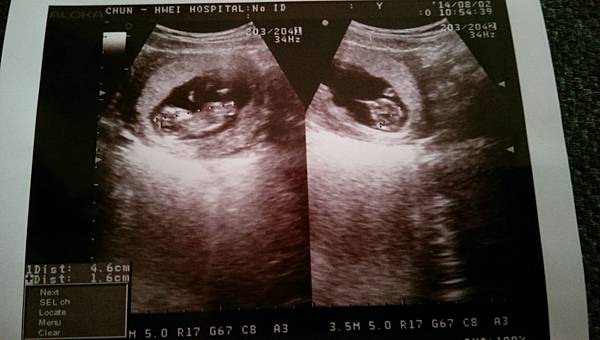

原本都是在永福橋下的鍾婦產科做檢查,不過後來決定到離娘家進的中和春暉醫院給呂醫師做產檢,也決定之後在這邊生產(離娘家也近)。

這周是安排第一次產檢的日子,抽血驗尿量血壓跟身高體重,看超音波的比鼻已經有人型了耶(看的出來嗎?)。

比鼻發育的很好,醫生調整了一下預產期提早到104/2/18剛好是除夕夜,大概是很想跟大家一起吃年夜飯,檢查完一切正常之後來到衛教師這邊,告訴我有一些自費項目可以做檢查,這些項目大致上之前就有爬文過,小心如我,寧願多花前檢查也不想要有一點的機率存在。說實話誰也不想生出有問題的寶寶呢?除了機率的問題,再來就是誰又能100%保證自己的祖先(?)們沒有過任何遺傳性疾病呢(隱性基因帶原)?